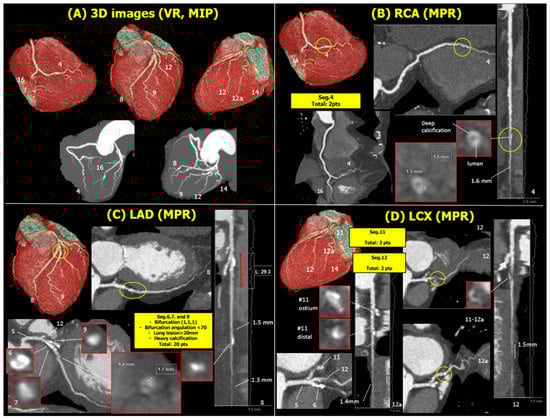

The CCTA was analyzed centrally by a core laboratory. Volume rendering assessment identified severe calcification in the proximal left anterior descending artery (LAD, Figure 1A). In the right coronary artery, there was a focal stenosis in the posterior descending artery (PDA, Figure 1B). In the left coronary artery, there was a severely calcified diffuse lesion involved in the bifurcation of the proximal LAD with the first diagonal (Figure 1C) and isolated stenoses in the proximal left circumflex (LCX) and ramus intermediate (RI, Figure 1D). In summary, the patient had calcified three-vessel disease (3VD) with a global anatomical SYNTAX score of 27.

Figure 1. Volume rendering and maximal intensity projection with numerical identification of the 16 segments reported in the Anatomical SYNTAX score. Volume rendering (A), multiplanar reformation, linear projection, and cross-sectional slices of interest with the anatomic SYNTAX score points annotated (BD). Abbreviations: 3D, three-dimensional; VR, volume rendering; MIP, maximal intensity projection; RCA, right coronary artery; MPR, multiplanar reformation; LAD, left anterior descending artery; LCX, left circumflex artery.